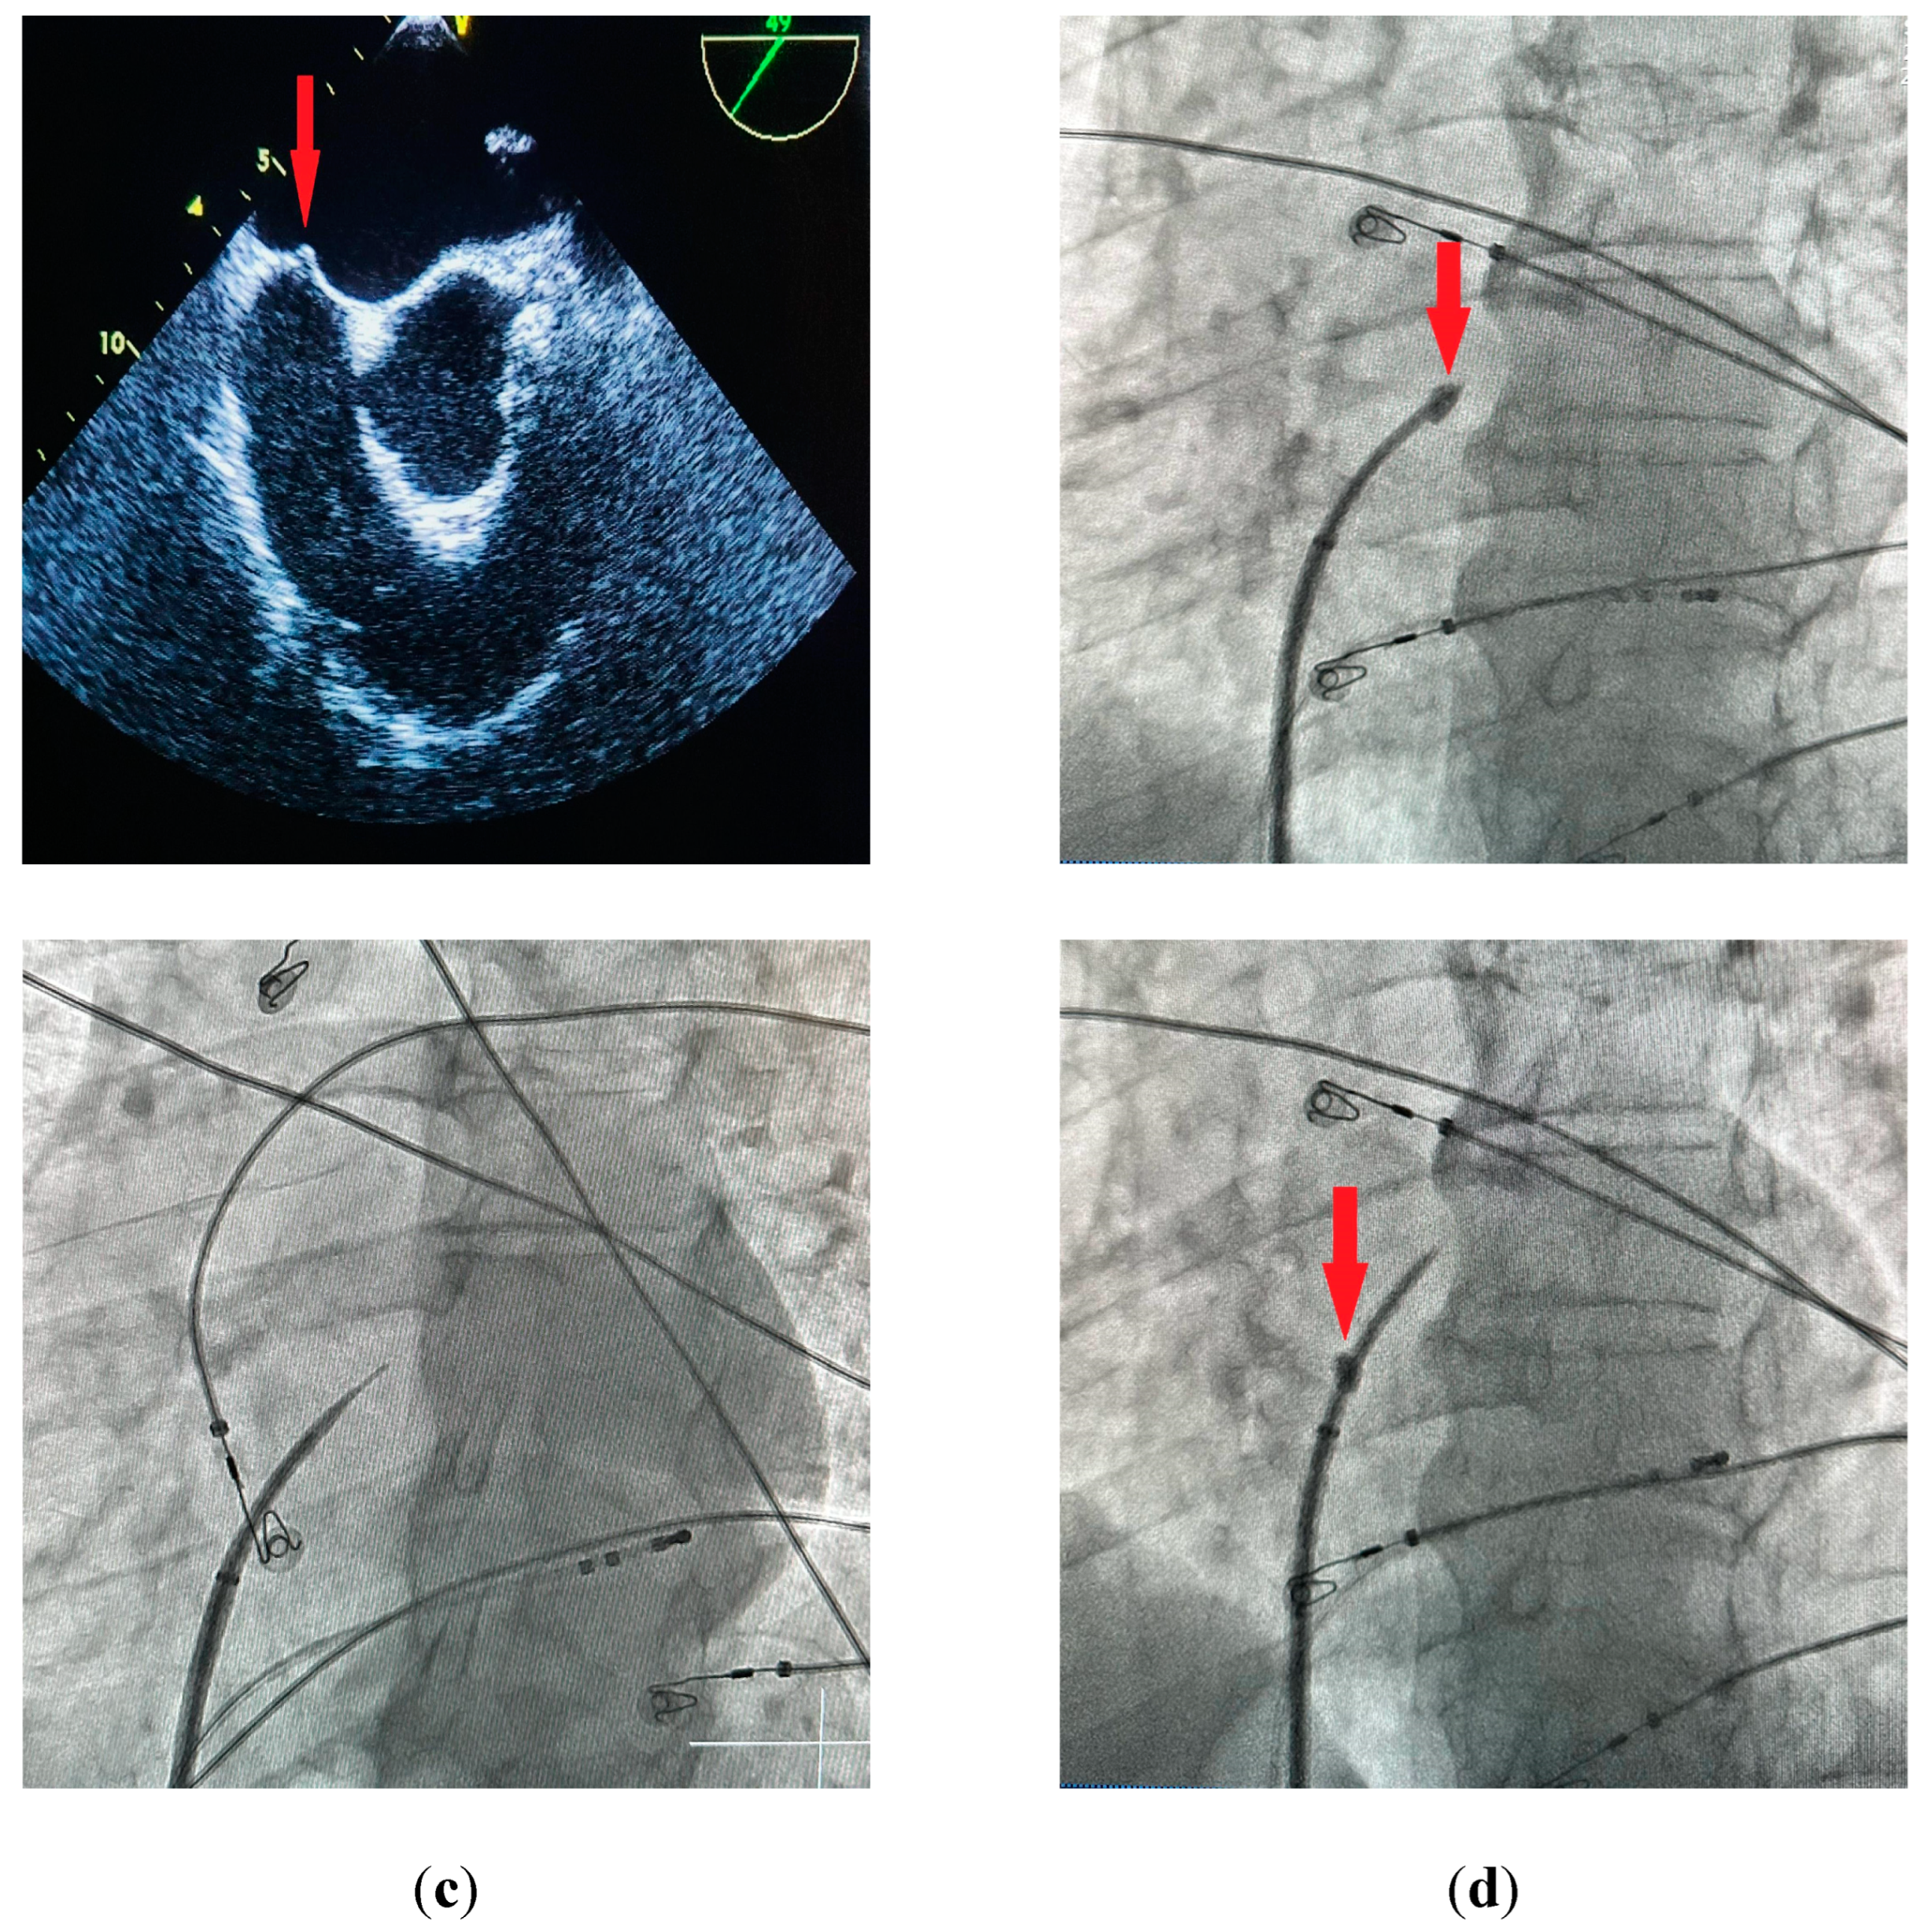

The standard technique for performing a TSP under fluoroscopic guidance involves obtaining venous access through the right femoral vein and placing a J-shaped guidewire into the superior vena cava. After advancing a transseptal sheath with a dilator over-the-wire into the superior vena cava, the guidewire is replaced with a transseptal needle with a stylet inside of it to avoid additional friction. After advancing the needle just below the tip of the dilator the stylet is removed and a syringe with contrast is connected to the needle. The System is then rotated to 4-5 o’clock (Figure 1a) and pulled down into the right atrium under the anteroposterior (AP) fluoroscopic view. Two “jumps” are encountered on the way down into the desired position on the interatrial septum - the first one after dropping from superior vena cava into the right atrium, and the second one after reaching the fossa ovalis. The assembly should then be carefully advanced into the final position (Figure 1b). A catheter placed in the coronary sinus is used as a landmark for the puncture; a pigtail catheter placed in the aortic root may also be used for additional orientation. Derejko et al. recently reported that a guidewire positioned between the superior and inferior vena cava can serve as another landmark guiding the TSP, as it should be running in direct vicinity to the FO in mid right anterior oblique (RAO) view [26]. Two independent fluoroscopic angles are used to confirm the correct position on the interatrial septum (IAS). In a 40° RAO view the assembly should be aligned so that the needle runs parallel to the coronary sinus catheter (Figure 1c). After verifying the correct position in the RAO view the needle is advanced outside the dilator under a 30° left anterior oblique (LAO) view (Figure 1d) and contrast is administered in order to confirm reaching the left atrium. Direct pressure monitoring from the transseptal needle may also be used [27]. IAS tenting can usually be observed before the needle passes into the left atrium (Figure 2a,b). The sheath with a dilator is carefully advanced over the needle into the left atrium. The needle is then withdrawn and replaced with a guidewire that is usually placed deep inside the left superior pulmonary vein. At this point the transseptal sheath can be safely exchanged for a dedicated transseptal system depending on the procedure type. Other modalities for TSP include the utilization of transesophageal (TEE) [27] or intracardiac echocardiography (ICE) [28] for direct visualization of the needle and its orientation relating to IAS and other heart structures.

Figure 1. (a) Baseline position in the superior vena cava with the needle-dilator-sheath assembly rotated to approximately 4-5 o’clock, AP view (b) - final position on the fossa ovalis: AP view (c) RAO 40° view (d) - LAO 30° view before the puncture.